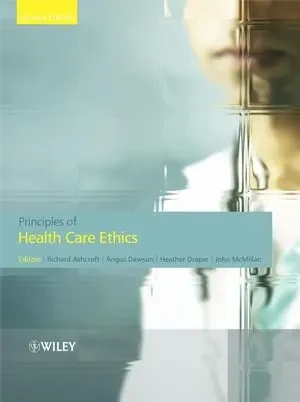

Books